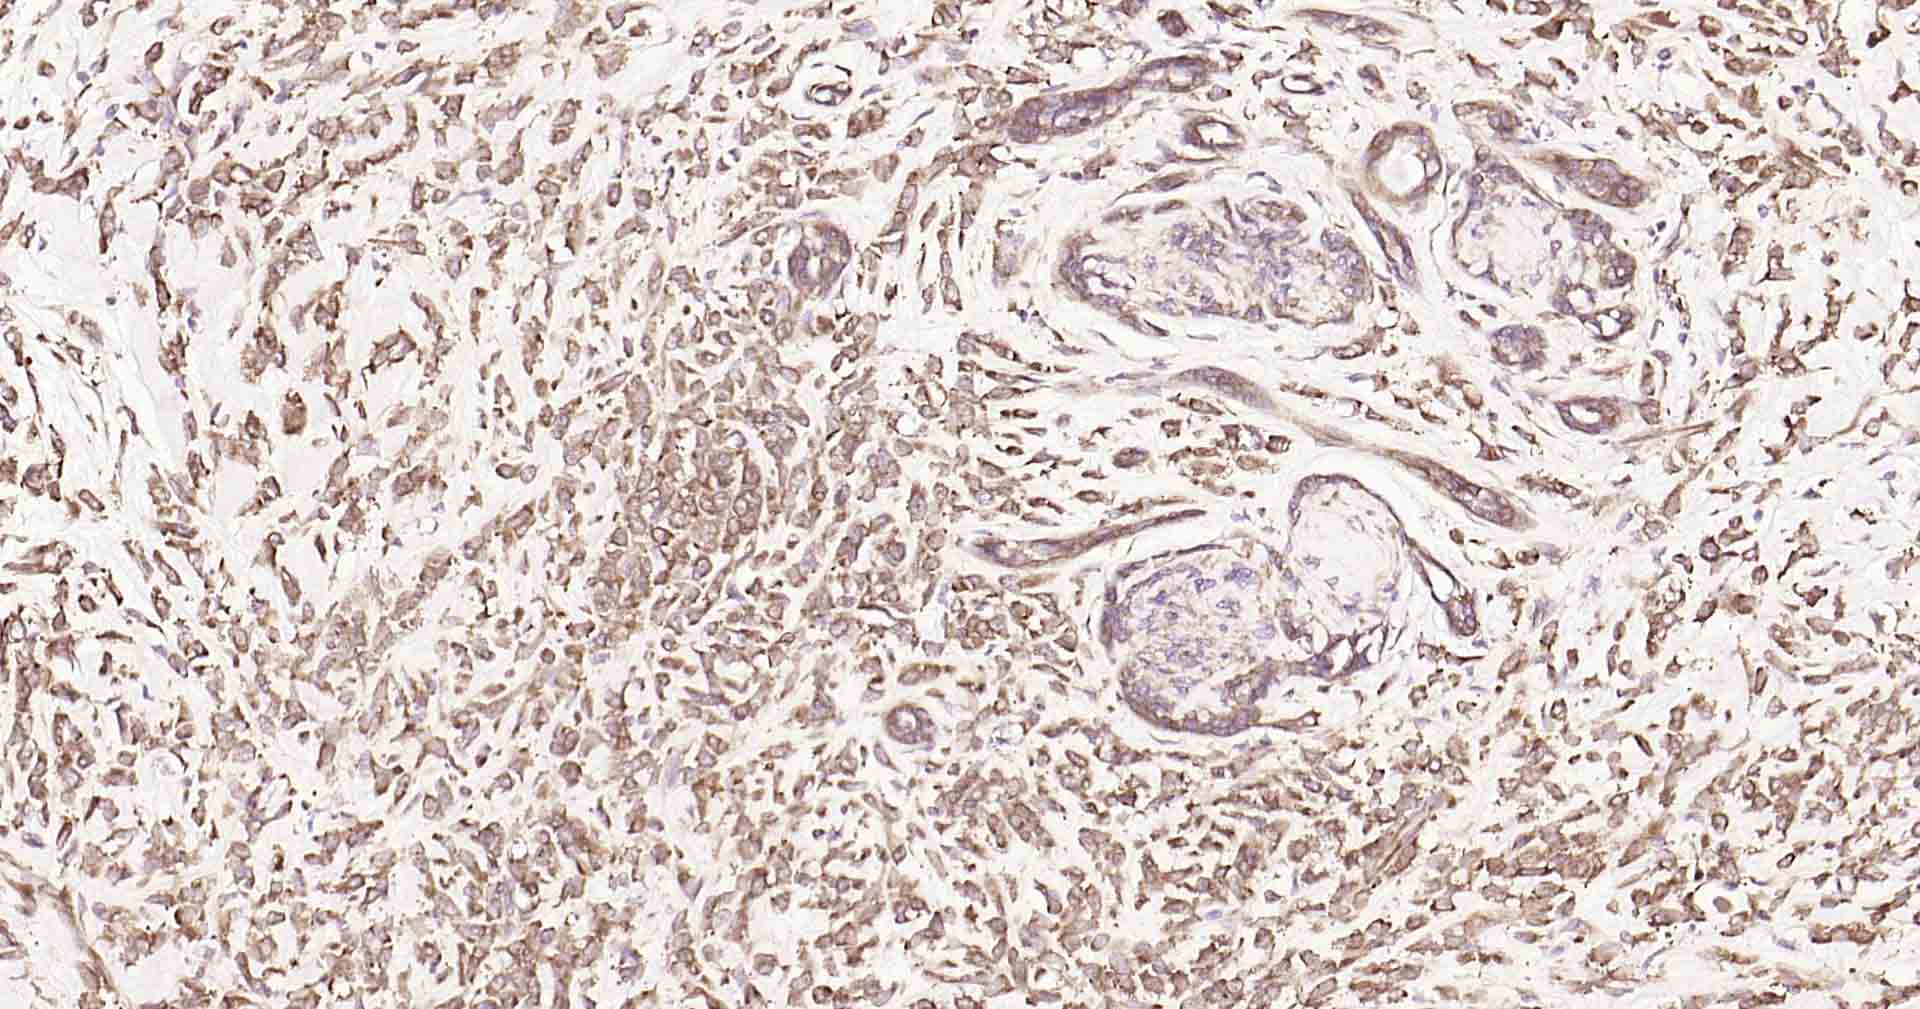

GADD153抗体-bs-20669RGADD153抗体-bs-20669RGADD153抗体-bs-20669RGADD153抗体-bs-20669RGADD153抗体-bs-20669RGADD153抗体-bs-20669RGADD153抗体-bs-20669RGADD153抗体-bs-20669RGADD153抗体-bs-20669RGADD153抗体-bs-20669RGADD153抗体-bs-20669R

IHC-PHuman, Mouse, RatCow1:50-200